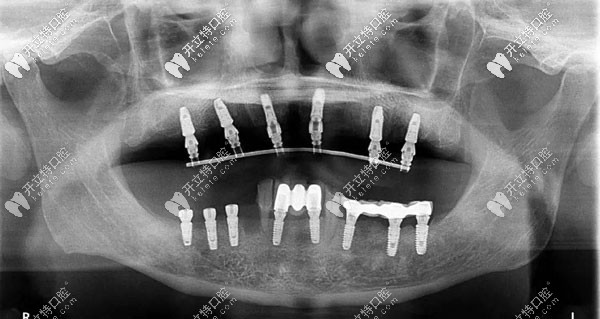

半口牙種植6或8顆植體全景圖

此外,all-on-6半口種植技術(shù),也就是種植6顆植體,配搭拱橋連冠,也是一個(gè)不錯(cuò)的選擇,還減輕了頜骨的負(fù)荷。

若牙槽骨吸收或萎縮的比較重,這樣醫(yī)生就會(huì)選擇在骨質(zhì)比較飽滿的位置,放4顆種植體做成斜拉橋似的設(shè)計(jì),來(lái)完成半口義齒的功能。